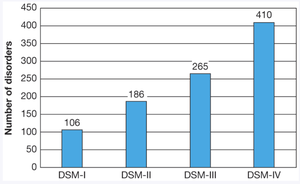

Modern Classification: The DSM

The Diagnostic and Statistical Manual of Mental Disorders (DSM) is the primary system for classifying psychological disorders in North America. The current edition is DSM-5-TR, which organizes disorders by symptom clusters and recognizes the spectrum of severity.

Some disorders, such as Asperger’s syndrome, have been reclassified under broader categories like autism spectrum disorder (ASD).

New diagnoses, such as prolonged grief disorder, reflect evolving understanding.

Problems with classification include defining what is truly 'maladaptive,' clinician bias, and the impact of labeling.